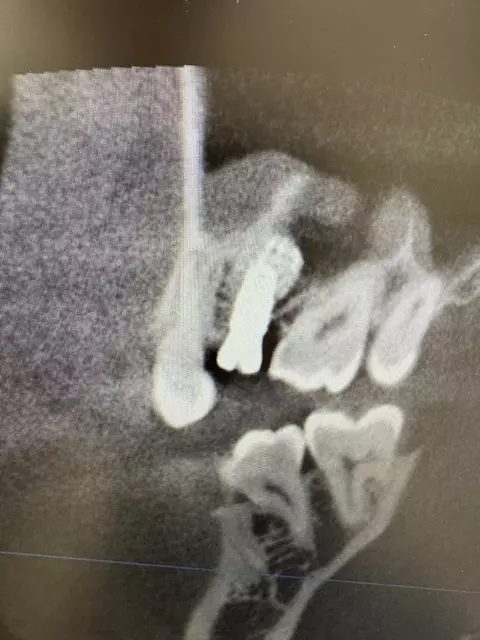

| 主訴 | 左下7番部 インプラント埋入 |

| 治療内容 | 左下7番部 インプラント埋入。 抜歯即時埋入。 抜歯後抜歯窩掻把。その後ワイドインプラント埋入。 |

時間は抜歯込みで20分程度でした。